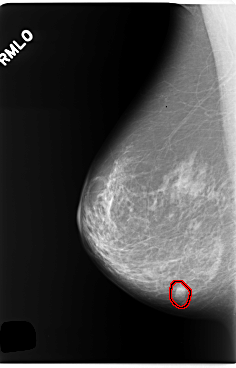

C_0255_1.RIGHT_MLO

RIGHT_MLO LINES 5880 PIXELS_PER_LINE 3776 BITS_PER_PIXEL 12 RESOLUTION 50 OVERLAY

FILE: C_0255_1.RIGHT_MLO.OVERLAY

TOTAL_ABNORMALITIES 1

ABNORMALITY 1

LESION_TYPE MASS SHAPE OVAL MARGINS CIRCUMSCRIBED

ASSESSMENT 4

SUBTLETY 5

PATHOLOGY BENIGN

TOTAL_OUTLINES 1

BOUNDARY